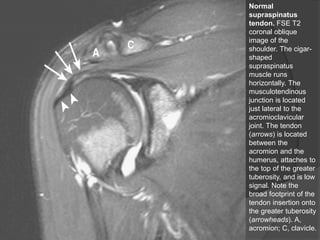

Normal

supraspinatus

tendon. FSE T2

coronal oblique

image of the

shoulder. The cigar-

shaped

muscle runs

horizontally. The

musculotendinous

junction is located

just lateral to the

acromioclavicular

joint. The tendon

(arrows) is located

between the

acromion and the

humerus, attaches to

the top of the greater

tuberosity, and is low

signal. Note the

broad footprint of the

tendon insertion onto

the greater tuberosity

(arrowheads). A,

acromion; C, clavicle.

Normal supraspinatus tendon. FSE T2 coronaloblique image of the shoulder. The cigar- shaped supraspinatus muscle runs horizontally. The musculotendinous junction is located just lateral to the acromioclavicular joint. The tendon (arrows) is located between the acromion and the humerus, attaches to the top of the greater tuberosity, and is low signal. Note the broad footprint of the tendon insertion onto the greater tuberosity (arrowheads). A, acromion; C, clavicle. Dr. Emanuel R. Dantas